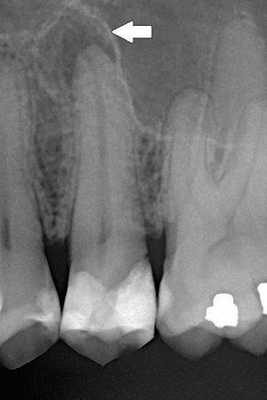

При пародонтозе с помощью реопародонтографии определяют сниженное количество капилляров, низкий уровень парциального давления кислорода, что свидетельствует об ухудшении трофики пародонта. Решающее значение при постановке диагноза «заболевания пародонта» имеют результаты рентгенографии. При патологии пародонта воспалительного характера на рентгенограмме обнаруживают участки остеопороза, деструкции костной ткани. При хроническом течении заболеваний пародонта наблюдается горизонтальная резорбция кости. Об абсцедировании свидетельствуют участки вертикальной деструкции.

Если есть подозрение на распространение процесса за пределы десны, необходимы дополнительные обследования, позволяющие оценить состояние корня зуба, костной ткани челюсти, пародонта. С этой целью широко используют рентгенографию [8] .

Чаще всего клиническая картина соответствует острому периодонтиту, за исключением того, что всегда рентгенологически выявляются изменения в тканях периодонта, характерные для той или иной формы периодонтита. [12]

Самый верный способ узнать о наличии недуга или подтвердить диагноз - сделать рентгеновский снимок. По нему стоматолог не только обнаружит воспаление, но и поймет, с какой именно формой он имеет дело в конкретном случае.

- Рентгенологическое обследование пролеченного зуба - осуществляется с целью контроля его состояния. Оно позволяет убедиться в эффективности лечения. Врач может рекомендовать дополнительное проведение этого этапа через каждые три месяца для изучения состояния кости.